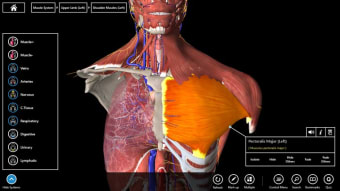

Mudah untuk memeriksa tubuh secara mendetail

Essential Anatomy sangat mudah digunakan. Fungsi pencarian adalah yang paling Anda butuhkan jika Anda sedang belajar meskipun Anda dapat bersenang-senang hanya dengan menjelajahi dan memutar tubuh. Anda dapat melepaskan lapisan otot dan jaringan untuk mengungkapkan apa yang ada di bawahnya, yang memberi Anda gambaran yang lebih baik tentang cara kerja tubuh daripada hanya membacanya di buku.

Selain itu, ada Alat penanda jika Anda hanya ingin menyimpan bagian tertentu yang ingin Anda kembalikan nanti dan Anda dapat mengisolasi tampilan tubuh berdasarkan jenis bagian (misalnya otot, arteri, vena, dll.).